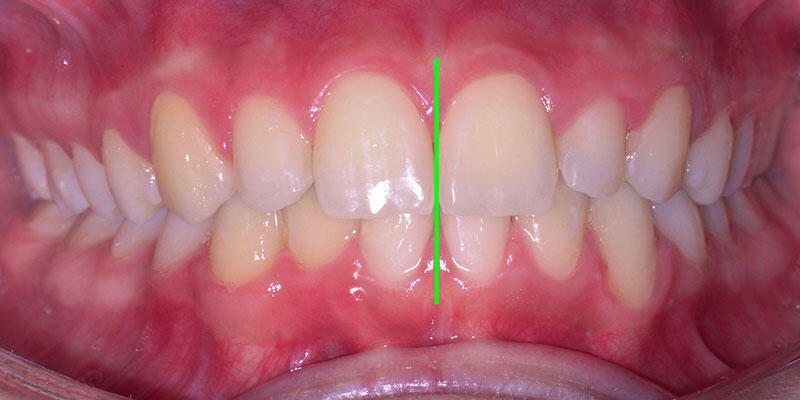

نمونه درمان ارتودنسی بدون کشیدن دندان: